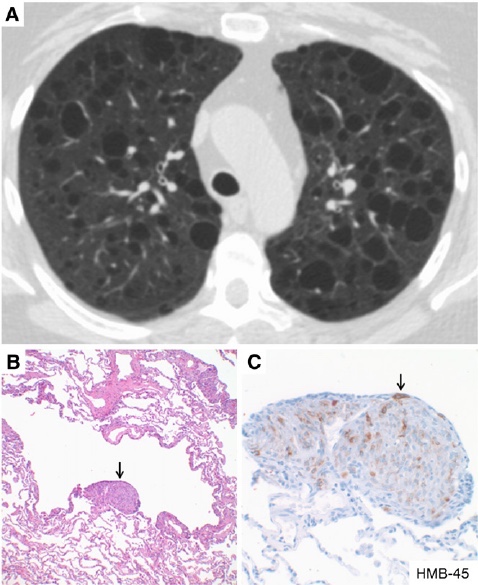

• CT ngực độ phân giải cao (HRCT): Hình ảnh đặc trưng là các nang khí lan tỏa hai phổi, đều đặn, kích thước đồng nhất, không tổn thương mô kẽ.

c. Sinh thiết phổi (trong trường hợp khó chẩn đoán)

Sinh thiết xuyên thành ngực hoặc nội soi phế quản để phân tích mô học.